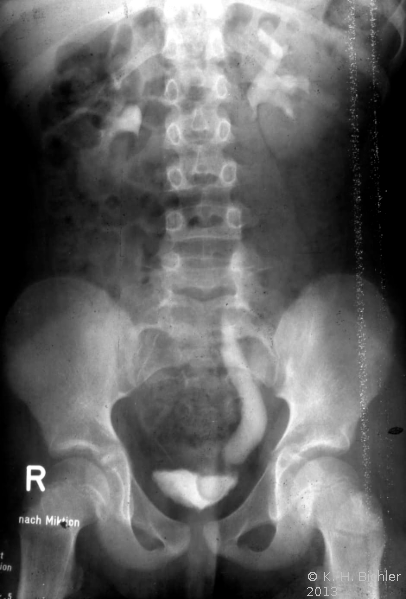

Bei dem 11 Jahre alten Mädchen mit Ureterozele und partiellem sekundärem Megaureter wurde wegen rezidivierender Harnwegsinfekte (Pyelonephritis) die Ureterozelenabtragung und Reimplantation durchgeführt und zwar mit Rücksicht auf das Lebensalter und um bei der vorgeschädigten linken Niere einen bei alleiniger Schlitzung drohenden Reflux zu verhindern (Abbildung 8).